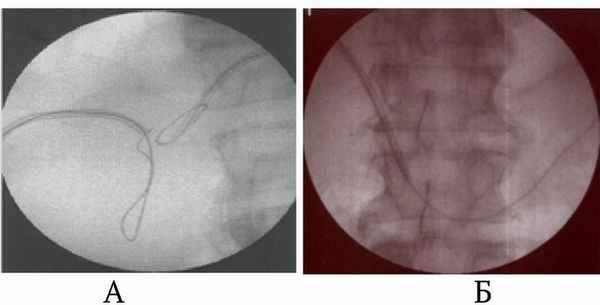

Рис. 1. Профилактика дислокации холангиостомических дренажей. Наличие металлических проводников в просвете дренажей, желчных протоков (А) и двенадцатиперстной кишки (Б)

Рис. 2. Восстановление дислоцированного дренажа ЧЧХС по проводнику, оставленному в желчных протоках. А – дренаж в поддиафрагмальном пространстве, проводник остался в просвете желчных протоков. Б – удален дренаж, В – проводник распрямлен, Г – по проводнику в желчные протоки введена игла УДПО, Д – дренаж введен в желчные протоки Учитывая, что большинство осложнений ЧЧХС возникает в результате дислокации дренажа [5], основное внимание уделяли надежной фиксации дренажа в желчных протоках. С этой целью в просвете дренажа и желчных протоков оставляли металлический проводник. Проводник вводили в двенадцатиперстную кишку или сворачивали в протоках, препятствуя его смещению (рис. 1). При этом кончик дренажа не упирался в стенку протока, что исключало «анкерный» механизм дислокации. Кроме того, при развитии неполной дислокации дренажа проводник еще оставался в протоке и по нему можно было вновь ввести выпавший катетер (рис. 2). В результате предпринятых мер профилактики в раннем периоде после ЧЧХС ни у одного больного не было полных дислокаций дренажа и желчеистечения в полость брюшины. Длительность госпитализации после ЧЧХС или ХС в стационарах по месту жительства составила 10.05±1,65 суток. Летальных исходов после успешно выполненного желчеотводящего вмешательства на этом этапе лечения не было. При длительных сроках наружного желчеотведения по холангиостоме у 28 (5,67%) больных произошла дислокация дренажа. Во всех наблюдениях дренаж удалось восстановить по свищевому ходу, оперативных вмешательств не потребовалось. Для восстановления выпавшего дренажа применяли специальные металлические канюли, имеющие оливовидное утолщение на рабочем конце. Катетеризировать желчный пузырь при холецистостомии удалось у всех 55 больных (100%). Технических сложностей и осложнений при чрескожной холецистостомии не отметили. Для холецистостомии использовали дренажи, фиксирующиеся с помощью нити, что у всех больных позволило избежать дислокации. Холецистостомические дренажи всем больным заменяли каждые 3 месяца в плановом порядке. Попытка реканализации желчевыводящих протоков была предпринята у 274 пациентов, что составило 51,6% от общего числа больных с холангиостомами. У 114 пациентов (41,61%) реканализация удалась с первой попытки. У 62 больных (22,63%) потребовалась повторная попытка реканализации. У 98 пациентов (35,77%) преодолеть зону окклюзии желчных протоков не удалось. У 1 больного во время реканализации отметили перфорацию общего желчного протока, которая клинически ничем не проявилась. Других осложнений, связанных с реканализацией желчных протоков, не отметили. Эндопротезирование желчевыводящих протоков выполнили 212 раз у 163 (30,7%) больных. В том числе у 8 человек эндопротезы установили в протоки обеих долей печени. В среднем эндопротезирование выпонияли через 7,6±1,3 суток после успешной реканализации желчных протоков. У 1 (0,6%) пациентки во время эндопротезирования отметили технические сложности, которые привели к неудачной попытке. В отдаленном периоде не было дислокации эндопротезов и окклюзии их за счет прорастания опухолью. У 1 больного (0,6%) после эндопротезирования развились множественные абсцессы печени. Выполнили пункционное лечение, исход благоприятный. У 1 больного эндопротез мигрировал в паренхиму печени. У 108 больных спустя различные сроки возникло нарушение проходимости эндопротеза, потребовавшее его замены. У 24 больных (22,2%) замену выполнили одномоментно. У 83 больных окклюзия эндопротеза привела к развитию холангита. Этим больным эндопротез заменили на наружно-внутренний дренаж, а после купирования холангита у 35 больных (42,2%) повторно установили эндопротез. У 1 больного через 10 месяцев после имплантации выявили закупорку эндопротеза и поддиафрагмальный абсцесс. Выполнили чрескожное дренирование абсцесса и замену эндопротеза на наружно-внутренний дренаж. Выводы. Чрескожное дренирование, реканализация и эндопротезирование желчных протоков, выполненные амбулаторно в условиях дневного стационара по разработанным методикам с помощью специально сконструированных инструментов, сопровождаются малым числом неудач и осложнений. Транспортировка больных перед и после чрескожных желчеотводящих вмешательствах, выполненных амбулаторно по разработанным методикам с помощью специально сконструированных инструментов, не приводит к развитию осложнений. Предложенная организация оказания медицинской помощи является эффективной в лечении больных с механической желтухой. Выполнение чрескожных желчеотводящих вмешательств в условиях дневного стационара улучшает доступность специализированной медицинской помощи данному контингенту больных